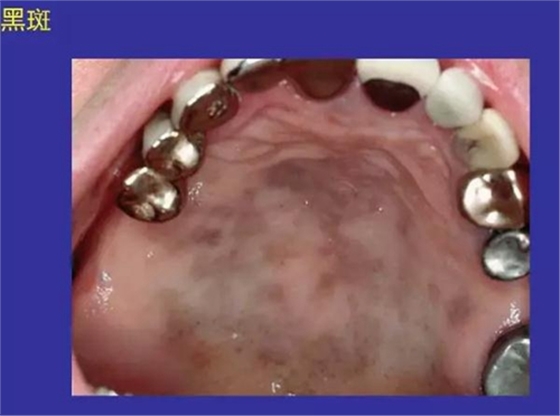

黑斑:阿狄森病、色素沉著、陳舊性出血

正??谇火つぜ俺R姴p圖